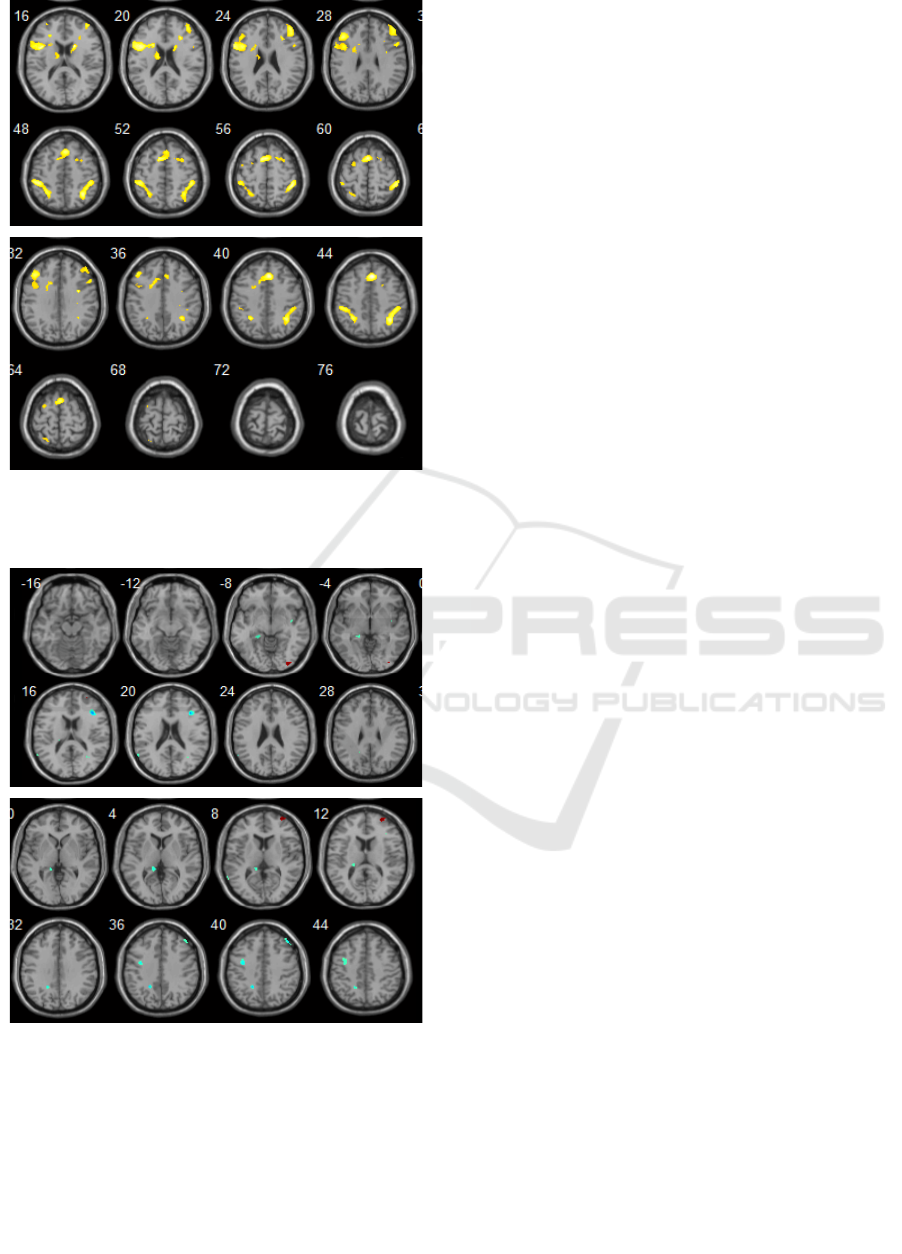

Figure 2: The control group. Activation sites (response to a

speech test) in the projection of brain structures: the isthmus

of the cingulate gyrus, insular lobes and parahippocampal

gyri.

Figure 3: The control group. Activation sites (response to a

count test): in the projection of brain structures: medial

prefrontal cortex, BA9, BA46, BA31, BA32.

(Figure 3).

When performing a speech test, in patients,

comparing to the control group, a decrease in

activation was found in the following areas: lower

parietal lobe bilaterally, insular lobules on the left

(BA13, MNI coordinates: -42 4 -1), lower frontal

gyrus on the left (MNI coordinates: -32 47 -1),

caudate nucleus (MNI coordinates: 14 10 11) on the

left, parahippocampal gyrus on the left (MNI

coordinates: 24 -9 -4). There was also a statistically

significant increase in activation in the projection of

the superior frontal gyrus on the left (BA 10, MNI

coordinates: 12 49 4), the medial prefrontal cortex

and the anterior cingulate gyrus, p <0.001, (Figure 5).

When performing count test (repeated count

operations), in patients, comparing to the control

group, a statistically significant increase in

activations was established in the following areas:

inferior parietal lobe, BA32 bilaterally (MNI

coordinates: -10 46 11; 14 40 11) , BA7 (MNI

coordinates: 23-60 60), BA9 on the right (MNI

coordinates: 35 39 31), insula (MNI coordinates: 44 4

10), middle frontal gyrus (MNI coordinates: 30 47

11), waist gyrus on the left (MNI coordinates: -3 36

11), p <0.001, (Figure 6).

Figure 5: Intergroup analysis results. Activation sites

(response to the presented speech test) in the patient group

compared to the control group. Increased (blue): in the

projection BA10 on the left. Decrease (red): in the

projection of the lower frontal gyrus on the left, the insula

on the left, the caudate nucleus, the parahippocampal gyrus

on the left (p <0.001).

Figure 6: Intergroup analysis results. Activation sites

(response to the presented sample test) in the patient group

compared to the control group: Increased (blue): in the

projection, left inferior parietal lobe BA9, left middle

frontal gyrus (p <0.001).